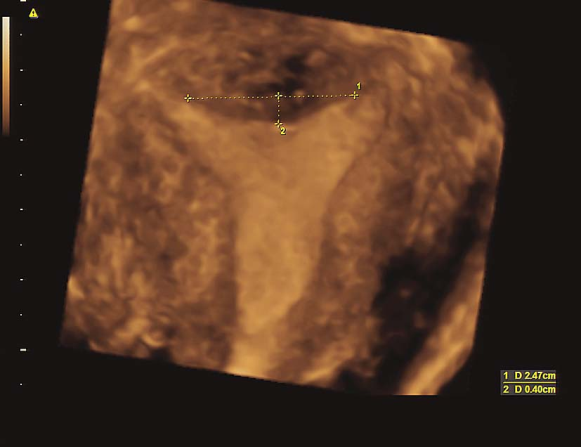

鞍状子宫三维超声

鞍状子宫碘油造影

(七)弓形子宫(arcuate uterus)

指宫底中间有一浅凹陷,但多大程度的凹陷可定义弓形子宫尚有争议。一般无症状。检查可扪及宫底部有凹陷。超声和磁共振检査及子宫输卵管碘油造影有助于诊断。一般不予处理。若出现反复流产时,应行子宫整形术。